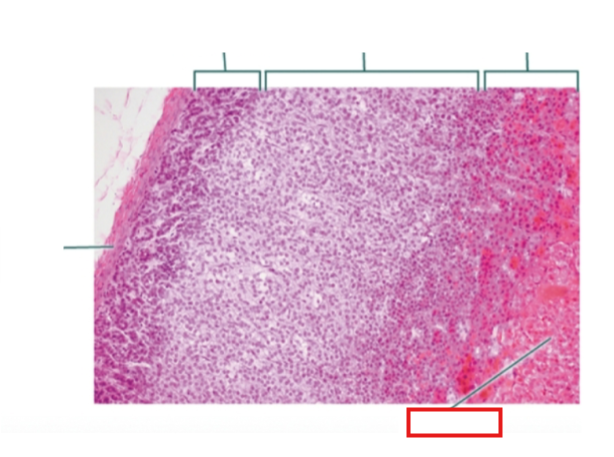

What structure is highlighted?

zona glomerulosa

What structure is highlighted?

zona fasciculata

What structure is highlighted?

zona reticularis

What structure is highlighted?

Capsule

What structure is highlighted?

medulla

What structure is highlighted?

capsule

What structure is highlighted?

zona glomerulosa

What structure is highlighted?

zona fasciculata

What structure is highlighted?

zona reticularis

What structure is highlighted?

adrenal medulla

What tissue is shown?

adrenal gland

What hormones are produced in the zona glomerulosa of the adrenal cortex?

mineralocorticoids; mostly aldosterone

What hormones are produced in the zona fasciculata of the adrenal cortex?

glucocorticoids; mostly cortisol

What hormones are produced in the zona reticularis of the adrenal cortex?

gonadocorticoids; androgens (most are converted to testosterone and some to estrogen)